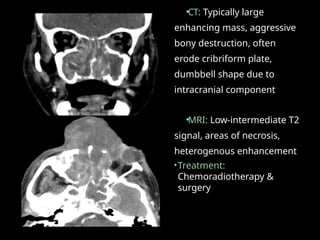

•CT: Typically large

enhancing mass, aggressive

bony destruction, often

erode cribriform plate,

dumbbell shape due to

intracranial component

•MRI: Low-intermediate T2

signal, areas of necrosis,

heterogenous enhancement

•Treatment:

Chemoradiotherapy &

surgery

• 56.

Undifferentiated sinonasal carcinoma •Rare non-squamous cell type tumor. • Elderly > 60 years • Aggressive & high propensity for distant metastasis; perineural spread. • Unlike ENB, it extends beyond sinonasal cavity.

• 57.

•CT: Typically large enhancingmass, aggressive bony destruction, often erode cribriform plate, dumbbell shape due to intracranial component •MRI: Low-intermediate T2 signal, areas of necrosis, heterogenous enhancement •Treatment: Chemoradiotherapy & surgery